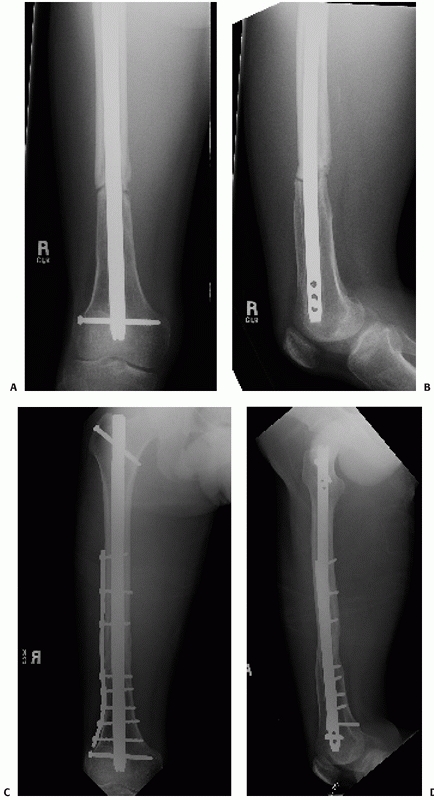

FIGURE 50-11 This 74-year-old male sustained a periprosthetic femoral shaft fracture after a motor vehicle crash (A, B). He had no previous problems with his hip prosthesis. The femur was plated using an extensile lateral approach (C-F).

Given the spiral fracture configuration, a direct fracture reduction with lag screw fixation was performed. A long neutralization plate that spanned the entire femur was used. |